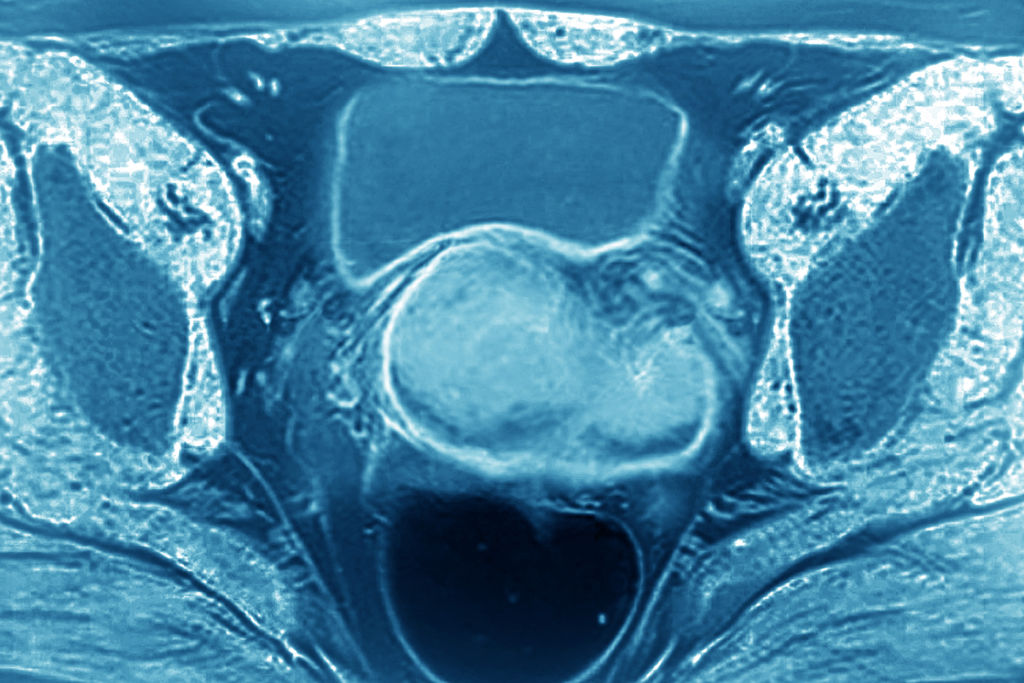

Uterine cancer is the main form of endometrial cancer, and the most common gynecological cancer, affecting about 3 percent of women. There’s no official tally of uterine cancer among the Ground Zero population because no agency has researched it. Attorneys and advocates who’ve kept track estimate at least 50 cases. Based on the number of female survivors and first responders and the prevalence of the cancer in the general population, there’s likely thousands of cases.